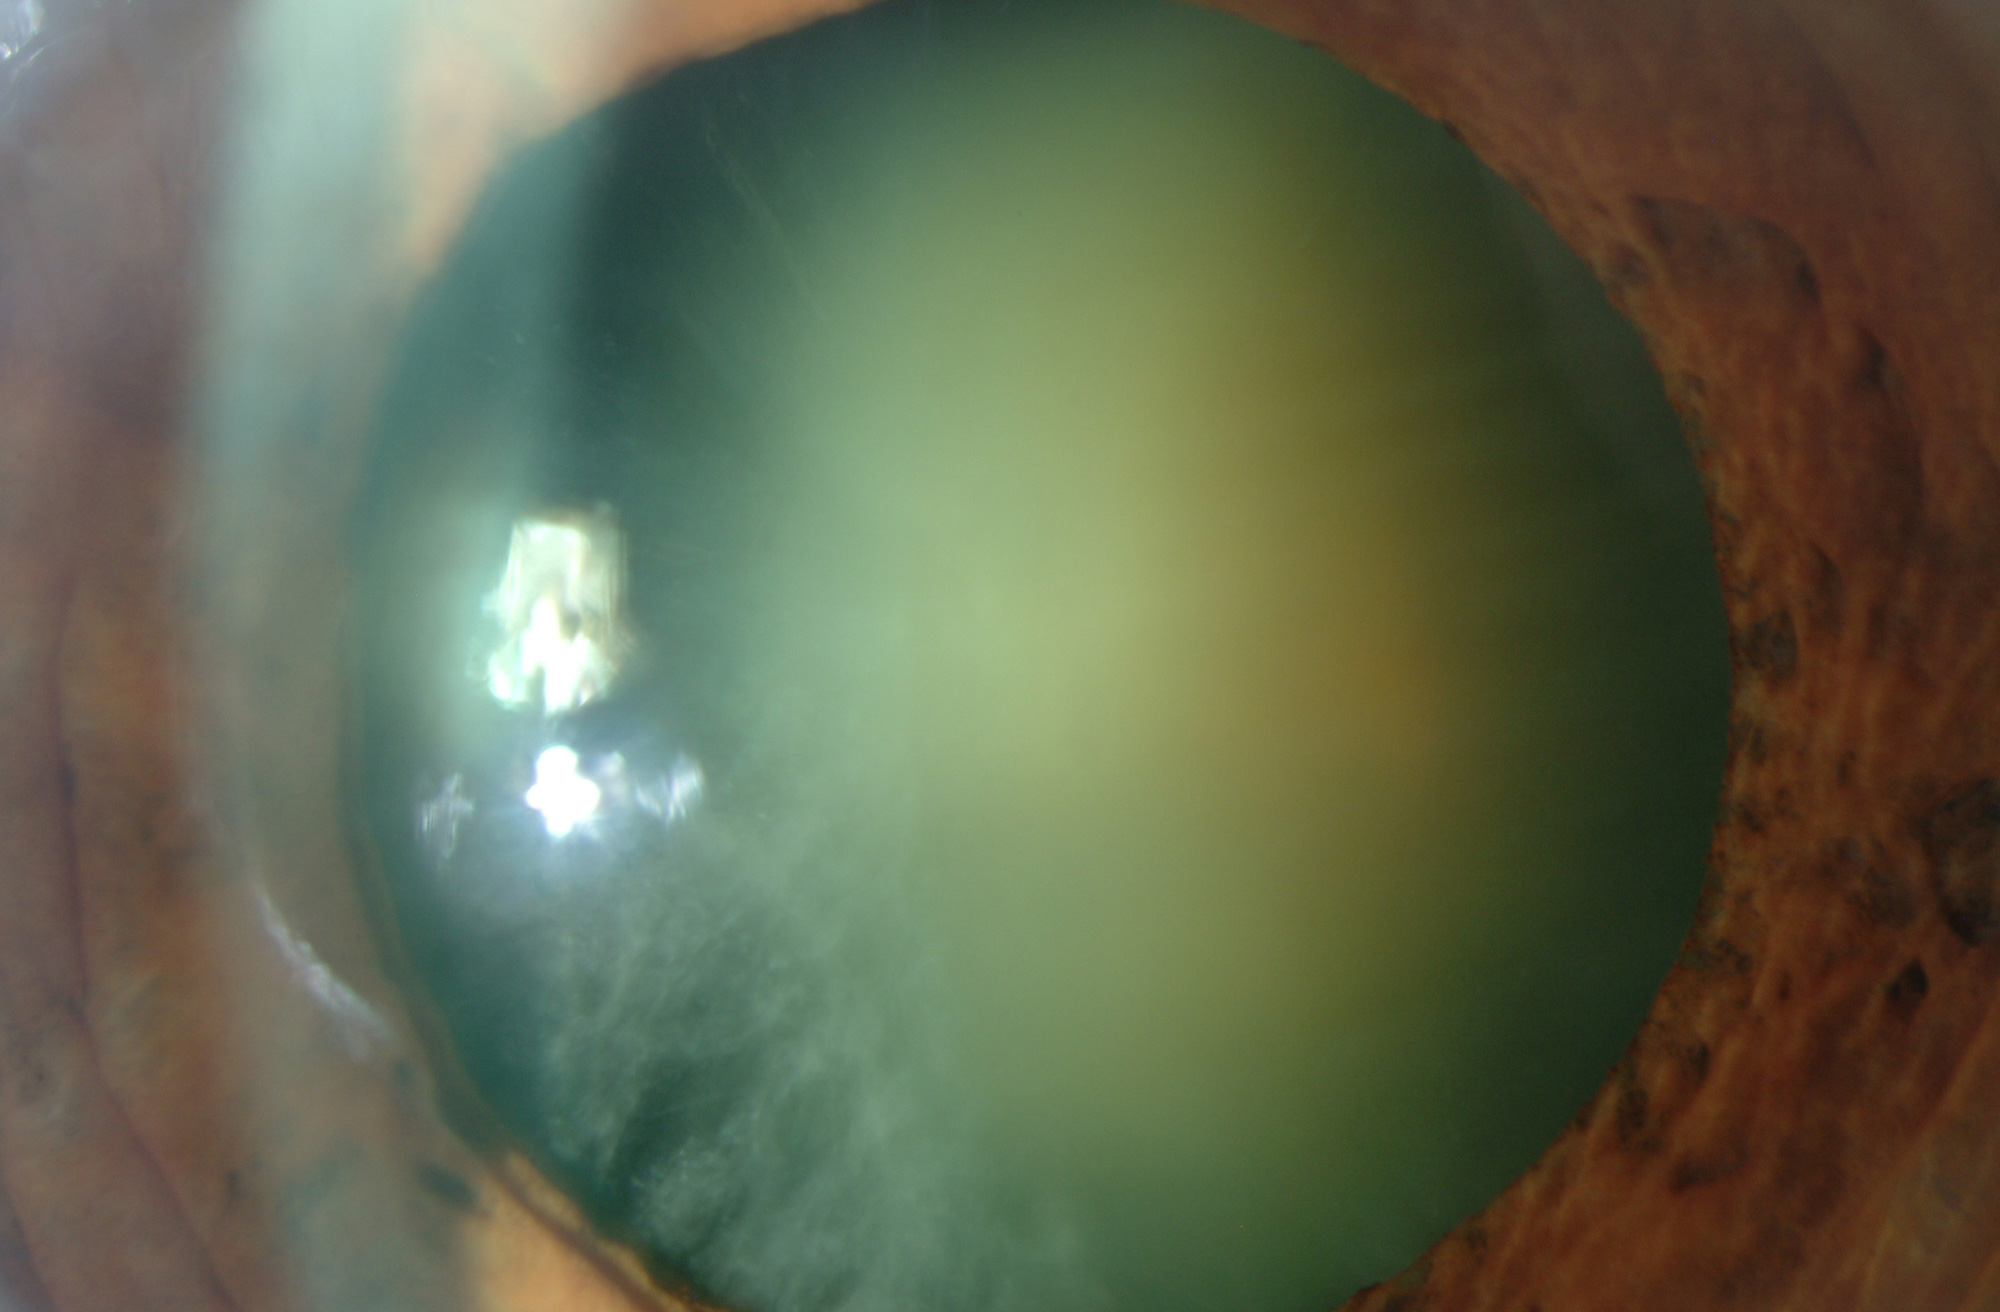

Cirugía de Catarata

La cirugía es la única opción terapéutica que permite devolver la vista al paciente con catarata.

La cirugía es la única opción terapéutica que permite devolver la vista al paciente con catarata.